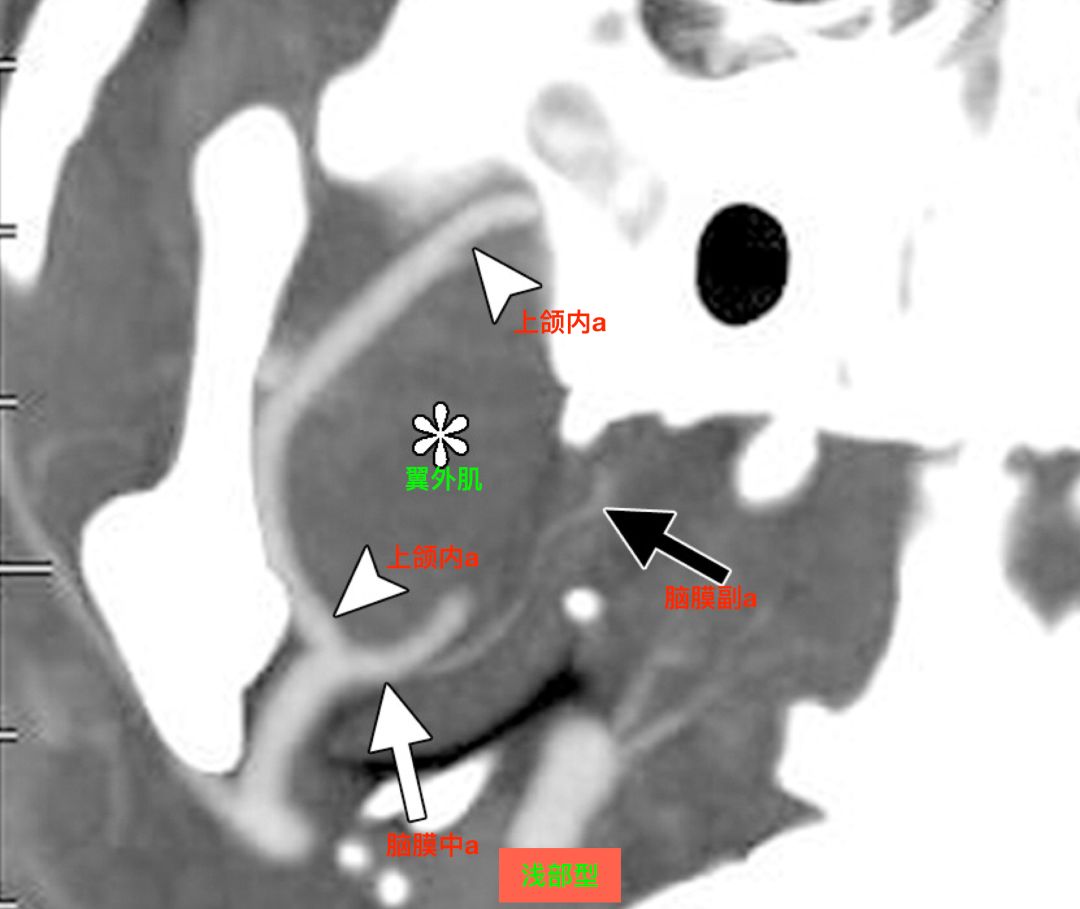

在CTA上,也可以区分浅部型和深部型。

CTA,浅部型,上颌内动脉走行于翼外肌浅面,脑膜中动脉和脑膜副动脉共干发出(Tanoue 2013)。

![]()